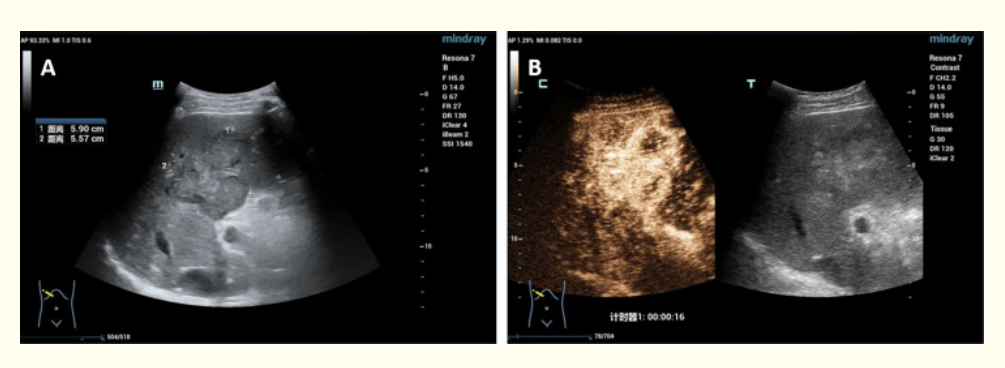

患者入院后进行进一步检查。脏器声学对比显示肝IV、V节实质低回声肿块,彩色多普勒血流显像(CDFI)显示血流信号。随后,增强CT和磁共振成像(MRI)显示肝脏V-VIII节段出现形态不规则的肿块(49 mm * 39.6 mm);肝门静脉和腹膜后淋巴结肿大,位于下腔静脉和腹主动脉之间的较大淋巴结(30.4 mm * 23.1 mm)。